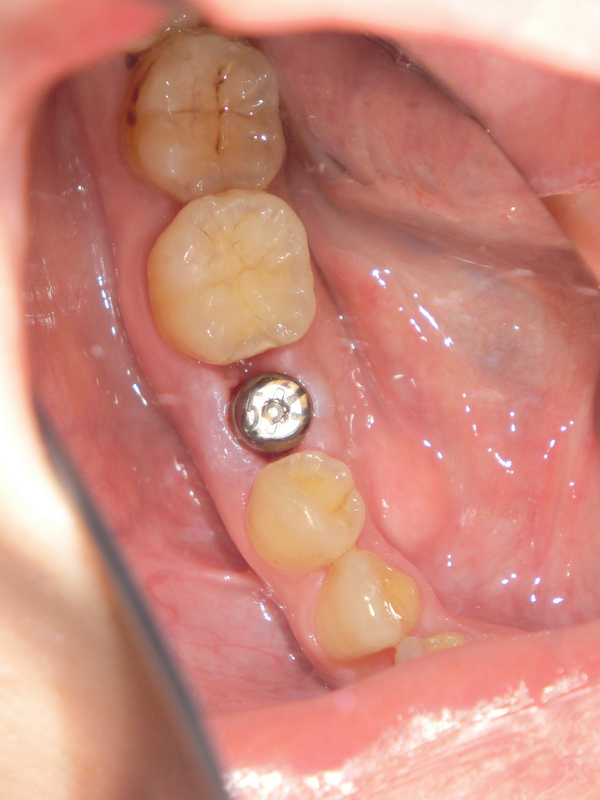

ではどのような治療法か、画像を用いて解説していきます。

まずはインプラントを入れる部位を肉眼的に確認します。そしてインプラントを埋め込む顎の骨と周囲の歯については、レントゲン写真やCTを用いてそのいい関係や性状を確認していきます。

レントゲンではこのように、インプラントが骨に植え込まれたことがわかります。

一連の工程で、部分麻酔を行っているため痛みは感じませんが、触られている感覚は残るので多少の違和感は感じることでしょう。1本につき、30分〜1時間で終わる作業です。